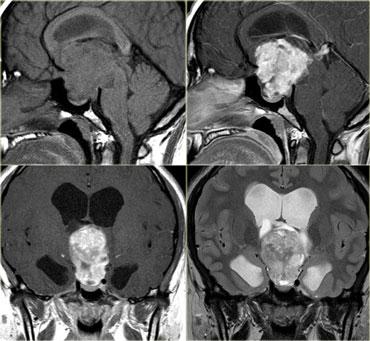

Bên trái là hình ảnh của một khối u nằm ở bán cầu não phải.

Mặc dù là khối u lớn nhưng hiệu ứng khối còn hạn chế.

Điều này cho thấy có sự phát triển thâm nhiễm rõ rệt, đặc điểm điển hình của u thần kinh đệm.

Lưu ý tính không đồng nhất trên cả chuỗi xung T2W và FLAIR.

Có ngấm thuốc không đồng nhất dạng đốm.

Tất cả các đặc điểm này điển hình cho GBM.

Hầu như không có khối u nào khác có biểu hiện tương tự như vậy.